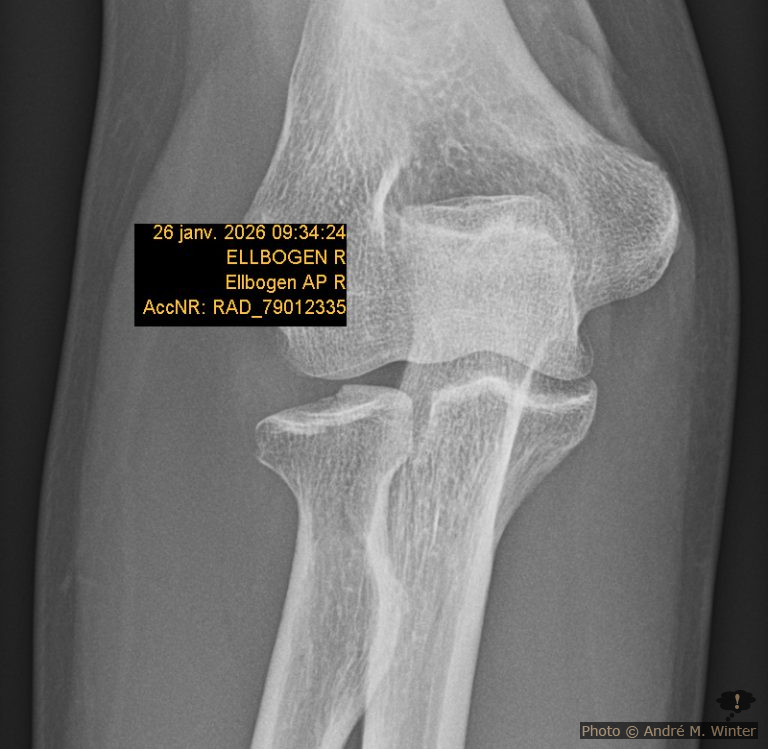

Radunfall mit Radiuskopfbruch Dezember 2025

Nun bin ich rund 3500 Kilometer mit dem neuen Radgefahren um mein lädiertes Knie fitt zu halten, bei jeden Wetter und allen Schwierigkeiten, es musste wohl einmal zu einem ernsteren Umfall kommen kommen. Bis jetzt handelte sich nur um Stürze im Wald auf Moos oder quasi im Stehen auf Eis. Dieser Abschnitt ist in Bezug…